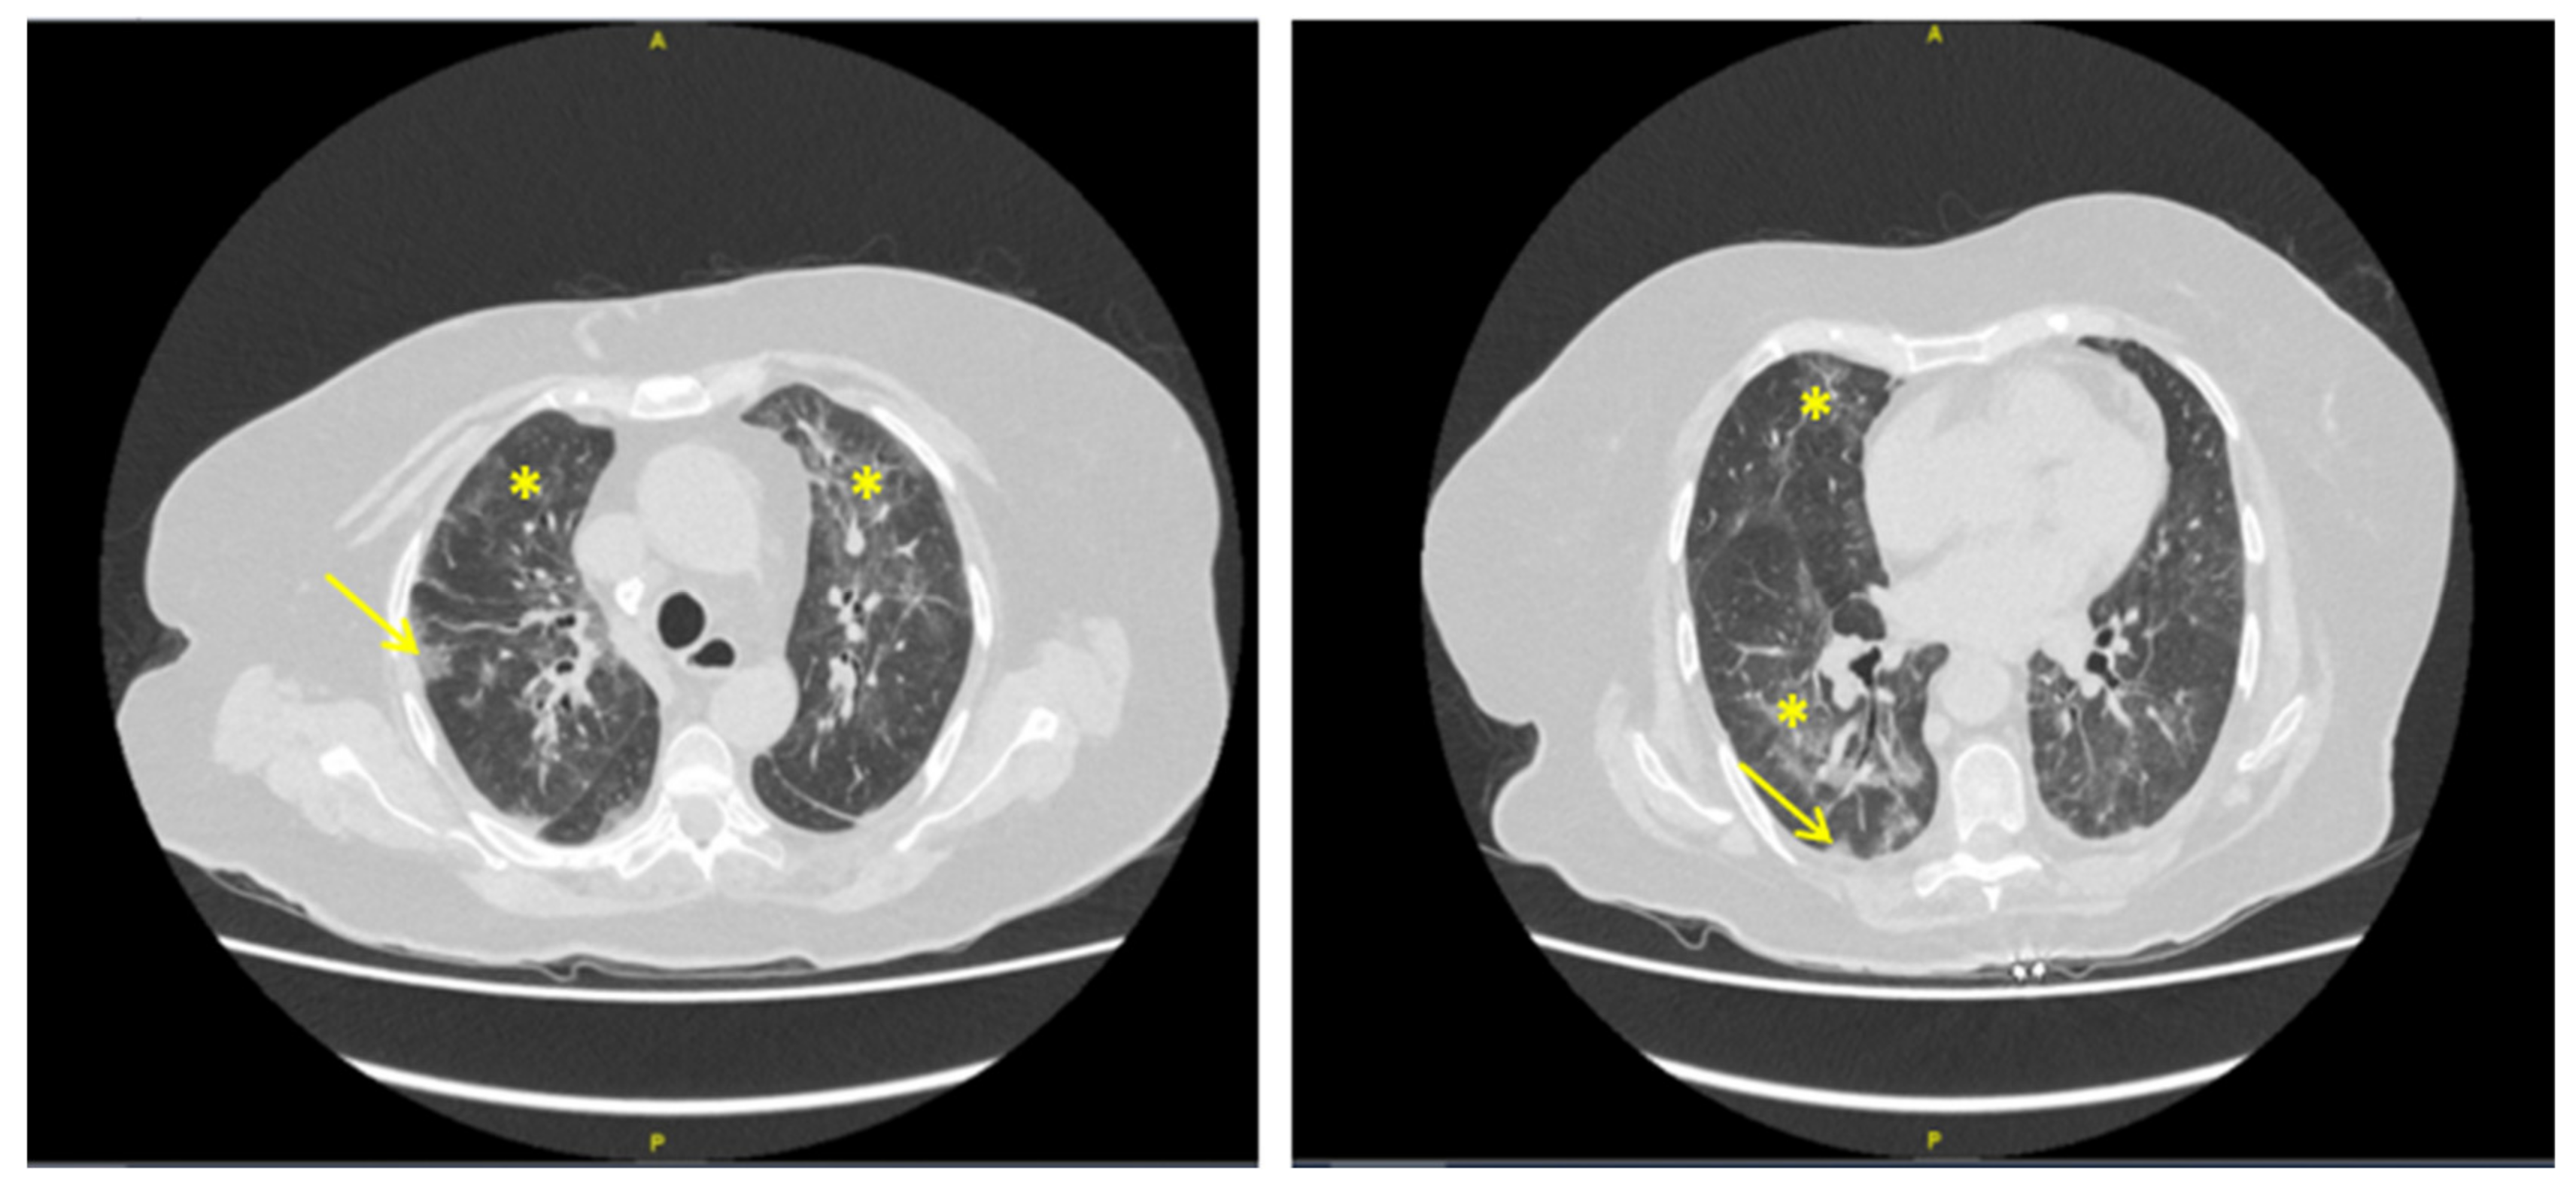

2. Case Presentation